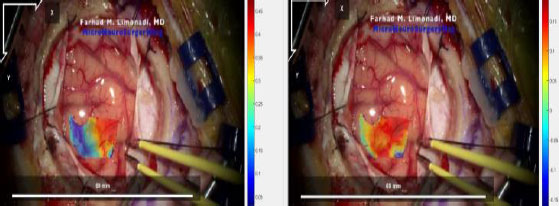

The sections of each video with stable (i.e., no movement of the camera) and uninterrupted frames of the pulsating surface tissue were identified and isolated. Each video section was then divided into a series of JPG images at a rate of twenty frames per second. These image files were then renamed according to Ncorr’s formatting requirements and analyzed. The resulting displacement and strain datasets were saved using MATLAB-compatible file formats. An example of the computed displacement plots can be seen in Fig. (7).

Analysis of the craniotomy videos revealed that strain maps throughout all four datasets were consistently aligned with surface topography and blood vessels. Fig. (9) demonstrates the shear strain from frame 139 of the Metastatic Tumor dataset [8]. Note that the transparency in this data plot was increased to emphasize those regions of strain which had a magnitude greater than 2%. The legend on the right notes that the darker red and darker blue sections of Fig. (9) had magnitudes between 0.04 (4%) and 0.06 (6%).

The bottom left to the top right of Fig. (9) displayed very low shear strain. This region had a mean shear strain magnitude of approximately 0.006 (0.6%).

However, the bottom right corner and the top right section of Fig. (9) displayed higher magnitudes of shear strain with absolute values between 0.04 (4%) and 0.06 (6%). Furthermore, these areas are separated from the middle region by blood vessels. Note that the relevant blood vessels are highlighted in pink for clarity. This trend is seen throughout the strain data, as seen in Figs. (10 and 11), and across the different datasets, as demonstrated in Figs. (12 and 13).